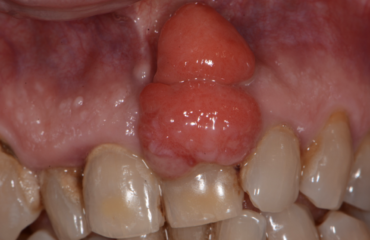

Parliamo di nuovo dell’epulide, tumore al 99% dei casi benigno, di origine parodontale (prende origine del legamento e non dalla gengiva) e di forma, il più delle volte, rotondeggiante e o trapezoidale.La si trova prevalentemente sui denti anteriori creando importanti inestetismi e a volte ostacolando le funzioni delle labbra.Il meccanismo per cui si sviluppa un’epulide […]